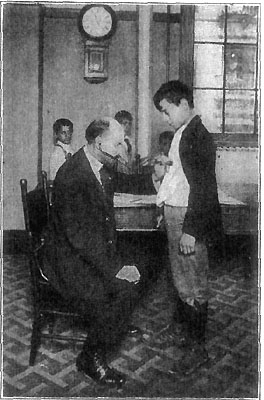

105 A Board of Health Examination for Working Papers

121 The School Physician Examining Heart and Lungs